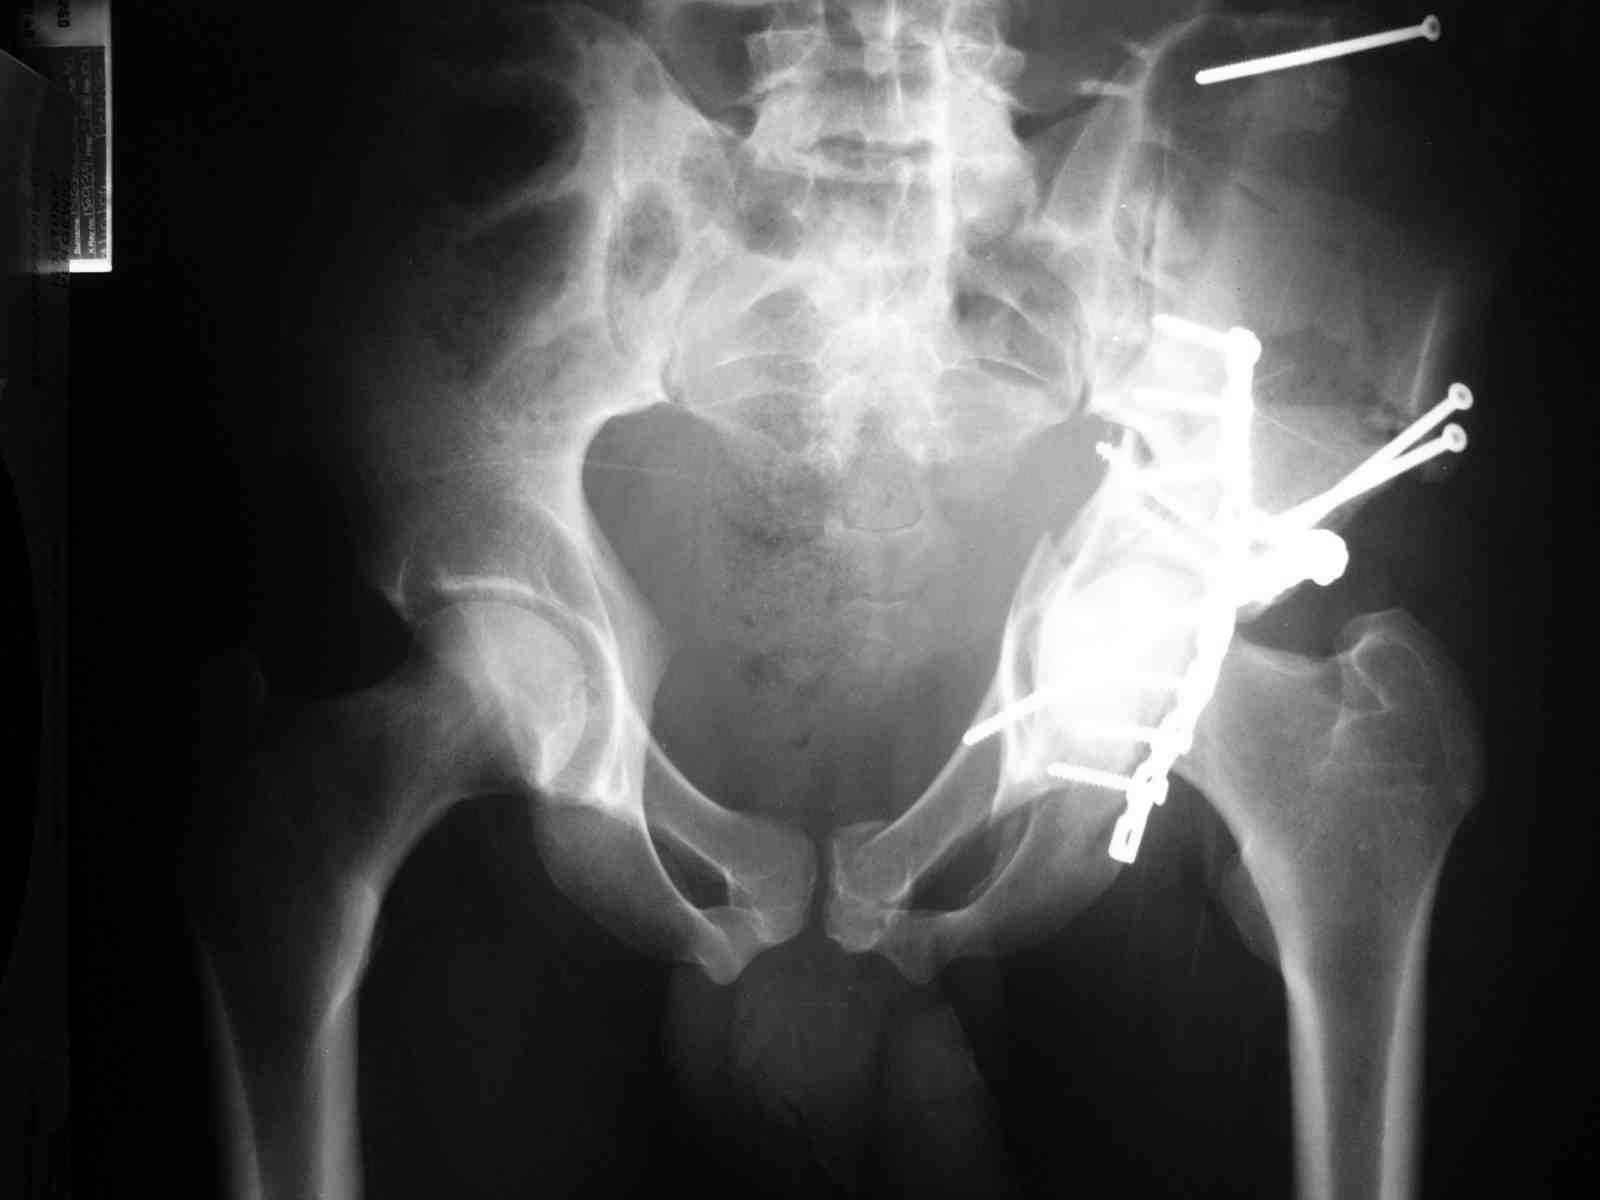

форуме и скелетном вытяжении. С репозицией и фиксацией задней колонны и отдельно задне-верхней стенки впадины проблем не возникло. Послеоп. Рг граммы в приложении. Если возникнут какие-либо дополнения или поправки - был бы признателен.

Спасибо за комментарии и рекомендации. Откровенно говоря, больного я прооперировал на прошлой неделе, через 5 дней после аварии и проблем с ним пока никаких нет, на удивление при достаточно обширной диссекции (илиофеморальный доступ) болей практически нет, так что больной самостоятельно садится в кровати, выполняет активные движения в оперированном суставе, сгибая до 60 градусов пока, далее с ассистенцией.

Причиной обращения к сообществу были возникшие непосредственно после операции сомнения и разочарования полученным качеством репозиции: а надо ли было трогать перелом вообще, репозиция передней колонны технически была очень сложна для меня, хотя реконструкции была в той же последовательности, что Д-р А.В.Рунков рекомендовал, в какой-то момент безуспешных манипуляций стал думать о *вторичной конгруэнтности*, которую не так давно обсуждали на